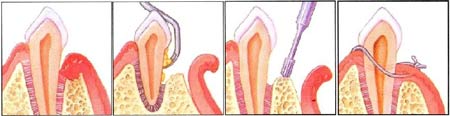

جراحی پیوند لثه (جراحی فلپ لثه)

در جراحی پیوند لثه، دندانپزشکان بافت لثه را از روی استخوان بلند کرده، در صورت لزوم جرم و پلاک آن قسمت را حذف کرده، سپس دوباره لثه را سر جای خود برگردانده و میدوزند تا بافت لثه محکم اطراف دندان قرار گیرد. این فرآیند حجم فضای بین لثه و دندان را نیز کاهش میدهد و در نتیجه فضای کمتری برای رشد مجدد باکتری باقی میگذارد.